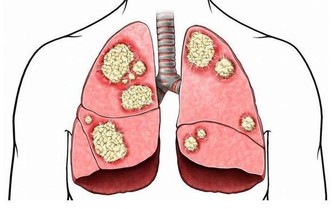

(7)活動不利

肝主筋,肝血不足,筋脈得不到充分濡養,就會影響關節活動的靈活度,出現肢體麻木、屈伸不利、手足震顫等症狀。